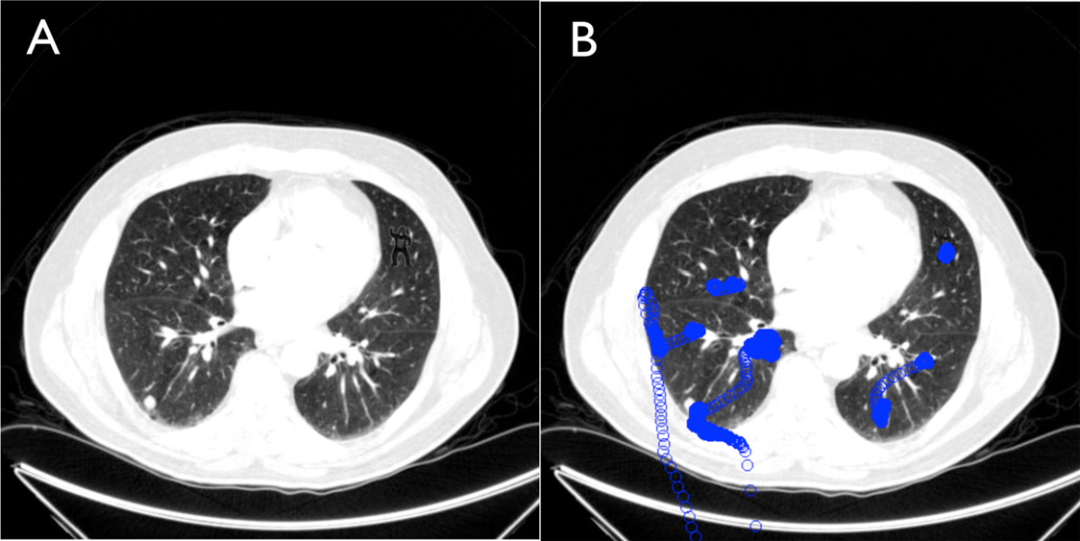

哈佛著名的“看不见的大猩猩”实验,在放射科场景中被多次复刻:

让经验丰富的医生筛查肺结节时,研究人员在CT切片中刻意植入一个微型大猩猩图案,结果高达83%的专业人士完全没看到。

经验训练我们锁定结节、钙化、肿块等特定目标,大脑的自上而下处理机制,会把“预料之外”的异常直接当作噪声抹除。你越专注于找某一种病变,就越容易漏掉另一种明显病变,这不是粗心,而是认知机制的天生缺陷。

A:嵌入大猩猩图案的胸部CT图像。 B:1名未报告看见大猩猩的放射科医生的眼动轨迹图。每个圆圈代表1毫秒内的眼动位置。